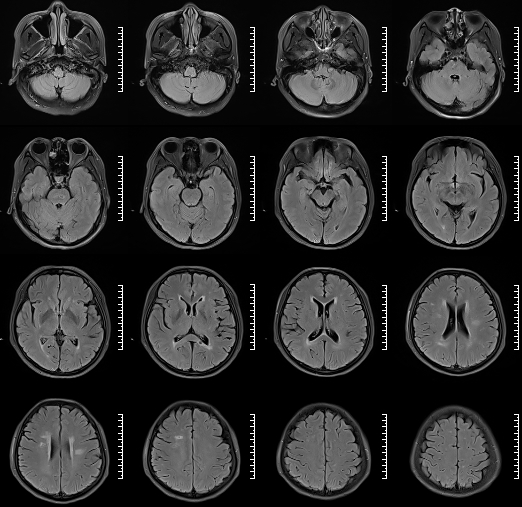

术前影像

HRMRI

左侧脑室旁亚急性期-慢性期脑梗死